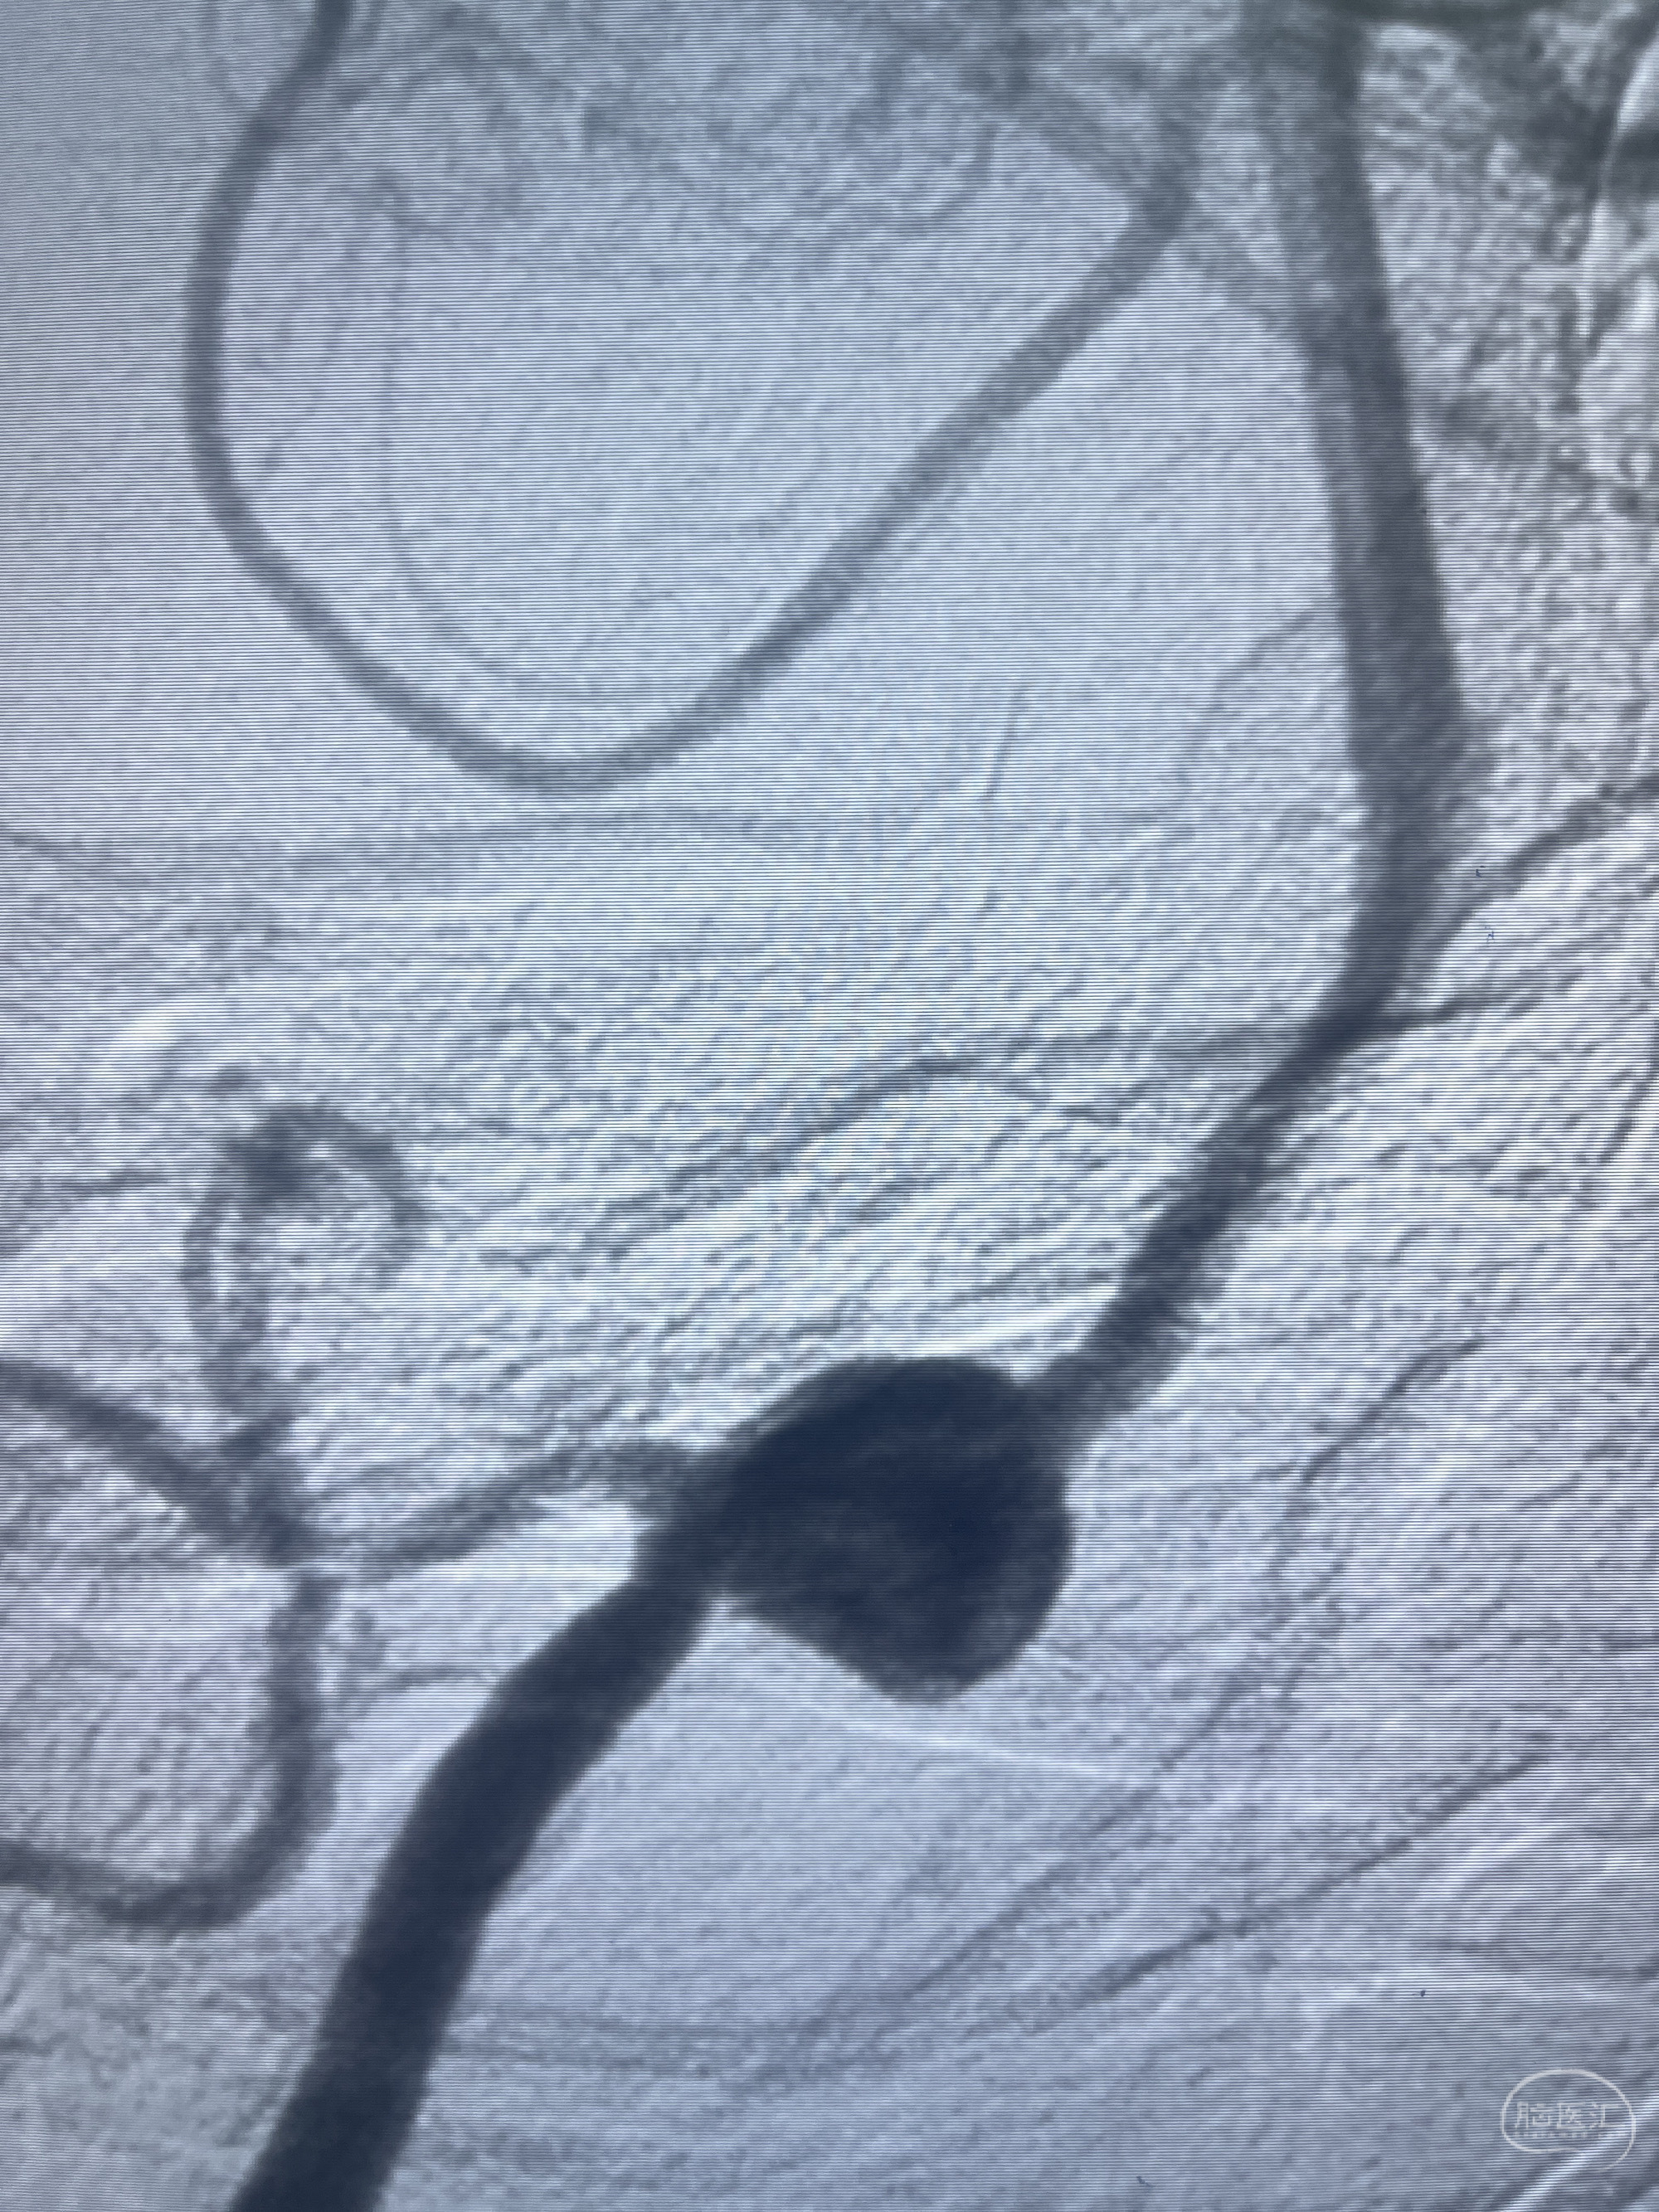

202.04.28脑血管造影:右侧大脑后动脉远段闭塞,右侧椎动脉V4段可见“囊状造影剂填充影”,大小7.64*7.65mm,可见PICA由动脉瘤发出;

1.普通支架辅助弹簧圈栓塞?

2.密网支架辅助弹簧圈栓塞?